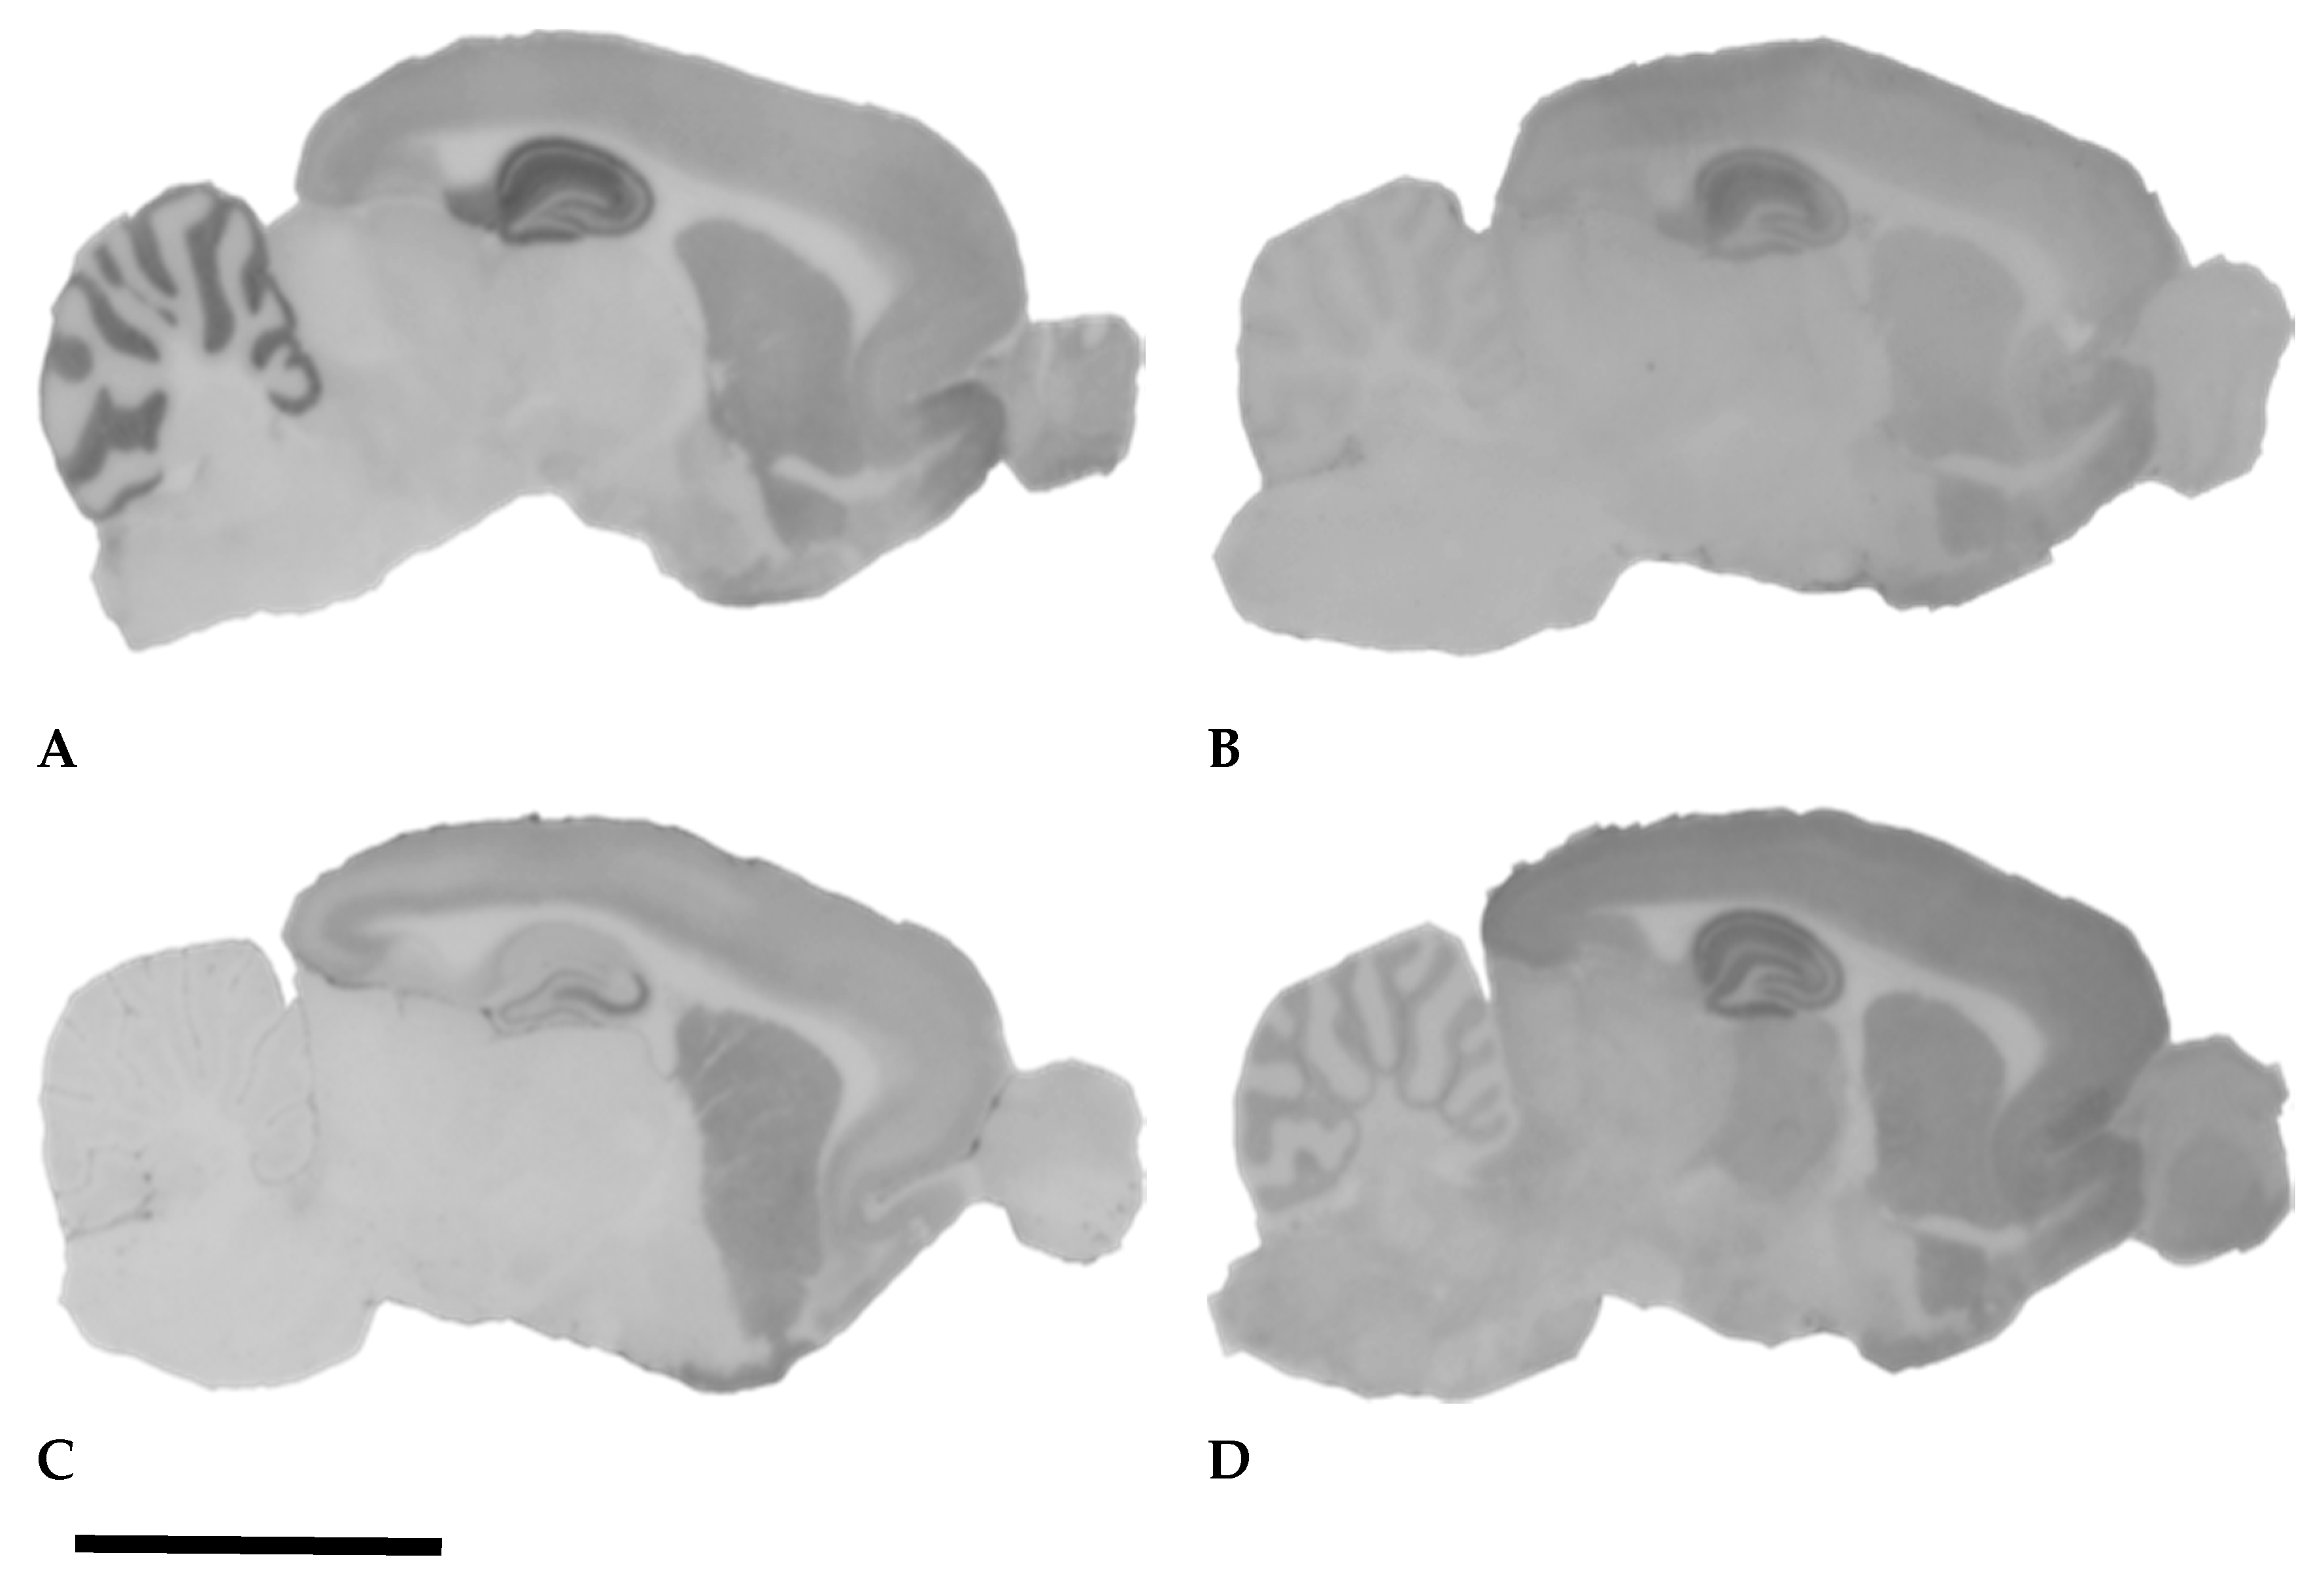

- Dobó, E.; Török, I.; Mihály, A.; Károly, N.; Krisztin-Péva, B. Interstrain differences of ionotropic glutamate receptor subunits in the hippocampus and induction of hippocampal sclerosis with pilocarpine. J. Chem. Neuroanat. 2015, 64–65, 1–11. [Google Scholar] [CrossRef] [PubMed]